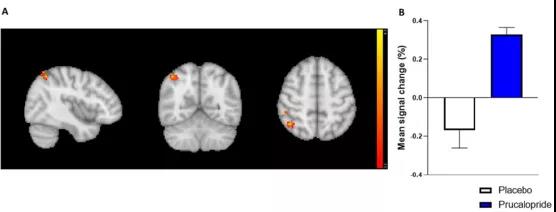

?牛津科學家發(fā)現(xiàn):通便也能通記憶,這種藥物或可促認知作用

眾所周知,很多精神疾病常常伴隨著認知功能障礙,認知障礙不僅局限于記憶缺陷,還包括學習、注意力、語言以及處理速度等方面的障礙。這類障礙會對生活質(zhì)量產(chǎn)生相當大的負面影響,所以迫切需要開發(fā)可以改善與精神疾病相關的認知缺陷的治療方法。